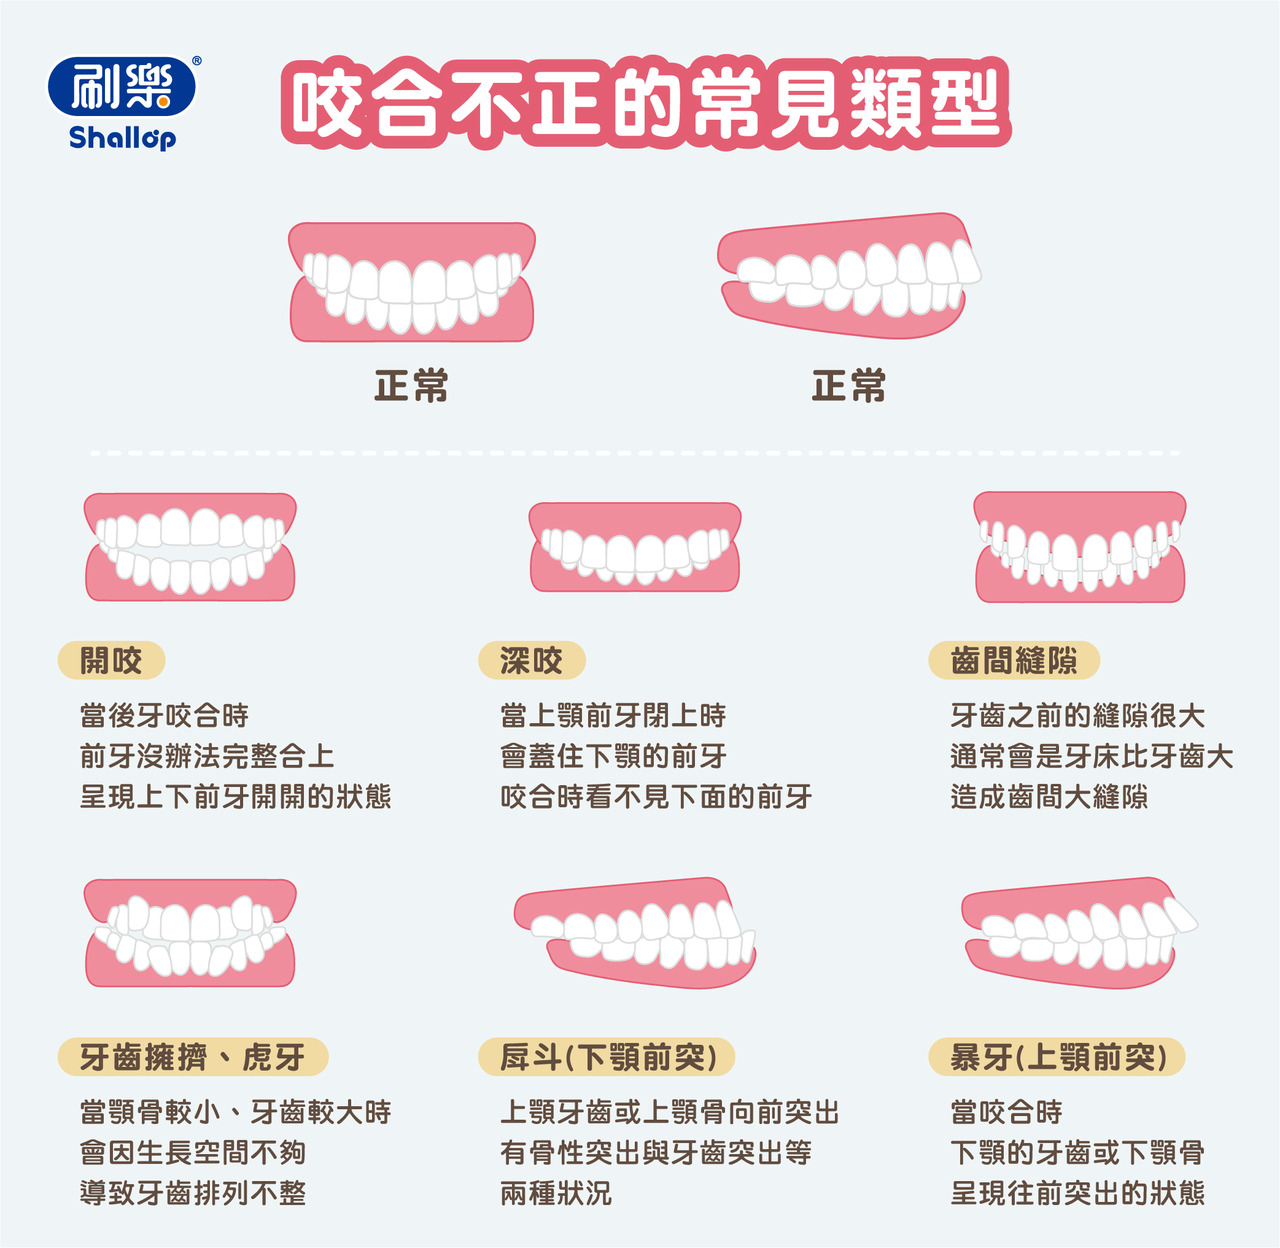

咬合不正一定要矯正嗎 刷樂shallop